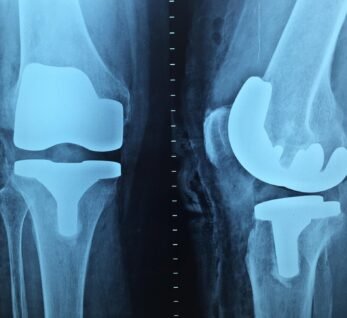

Advanced Orthopaedic Care

Long-term joint health and improved mobility for every patient.